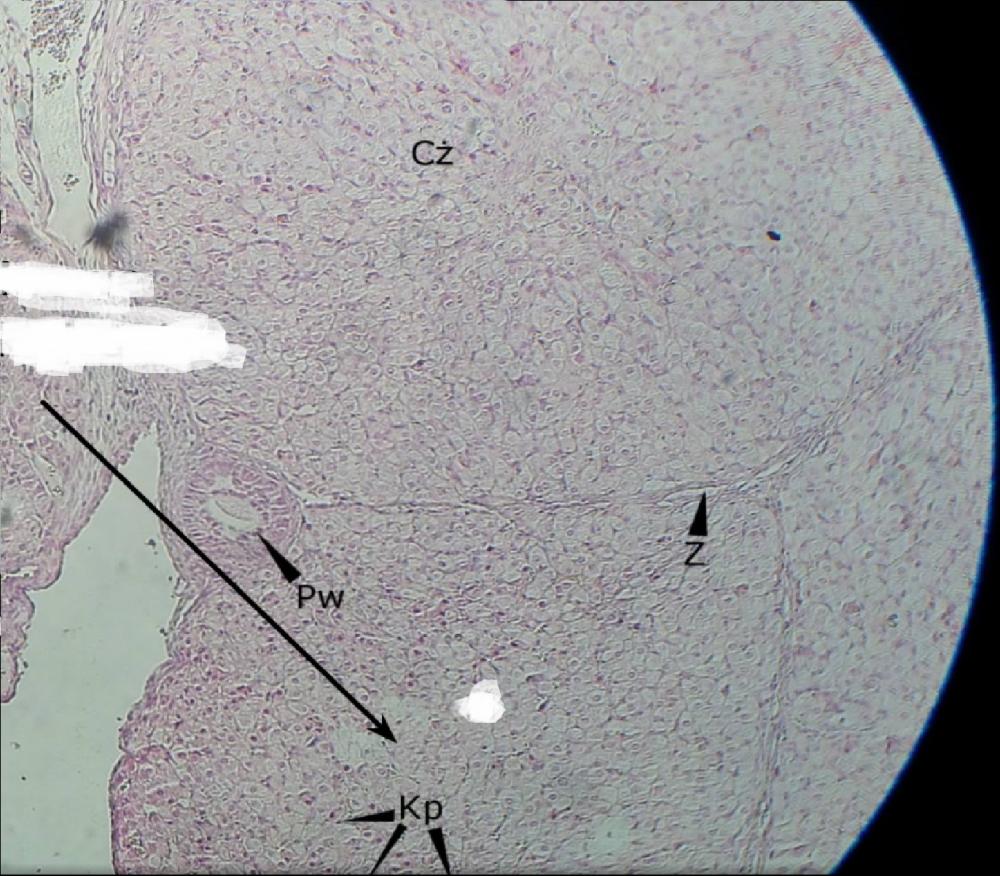

Pytanie 491

tkanka łączna (jajnik, ciałko żółte)

Pytanie 492

pęcherzyk wzrastający (jajnik, ciałko żółte)

Pytanie 493

komórki paraluteinowe - ciemne, wyróżniające się wśród jasnych (jajnik, ciałko żółte)

Pytanie 494

komórki luteinowe - jasne, jest ich bardzo dużo (jajnik, ciałko żółte)

Pytanie 500

otrzewna (macica)